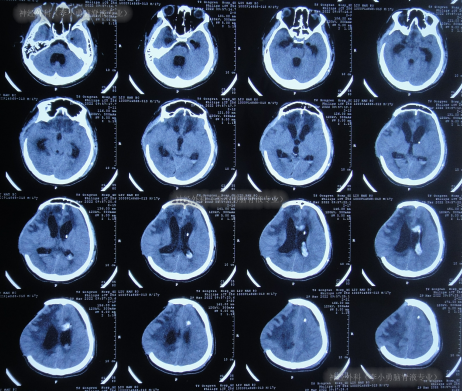

虽又再次出现脑积水但2022年5月5日(脑室腹腔分流术后38天),仍进行了右侧额颞顶部颅骨缺损修补术(图-12)。

图-12:2022年5月6日头颅CT

但颅骨修补术后1周即2022年5月13日(脑室腹腔分流术后45天),患者反而出现意识变差,由清醒变为嗜睡,肢体活动也变差,且肢体肌张力增高,查头颅CT(图-13)后给予保守治疗。

图-13:2022年5月13日头颅CT

该院继续治疗半月,但患者病情进一步加重为昏迷,期间3次查头颅影像(图-14)。

图-14:3次查头颅影像

因昏迷加重于2022年6月2日(颅骨修补术后27天即脑室腹腔分流术后65天),查头颅CT示仍脑积水(图-15);进行了腰椎穿刺示颅压较高。

图-15:2022年6月2日头颅CT